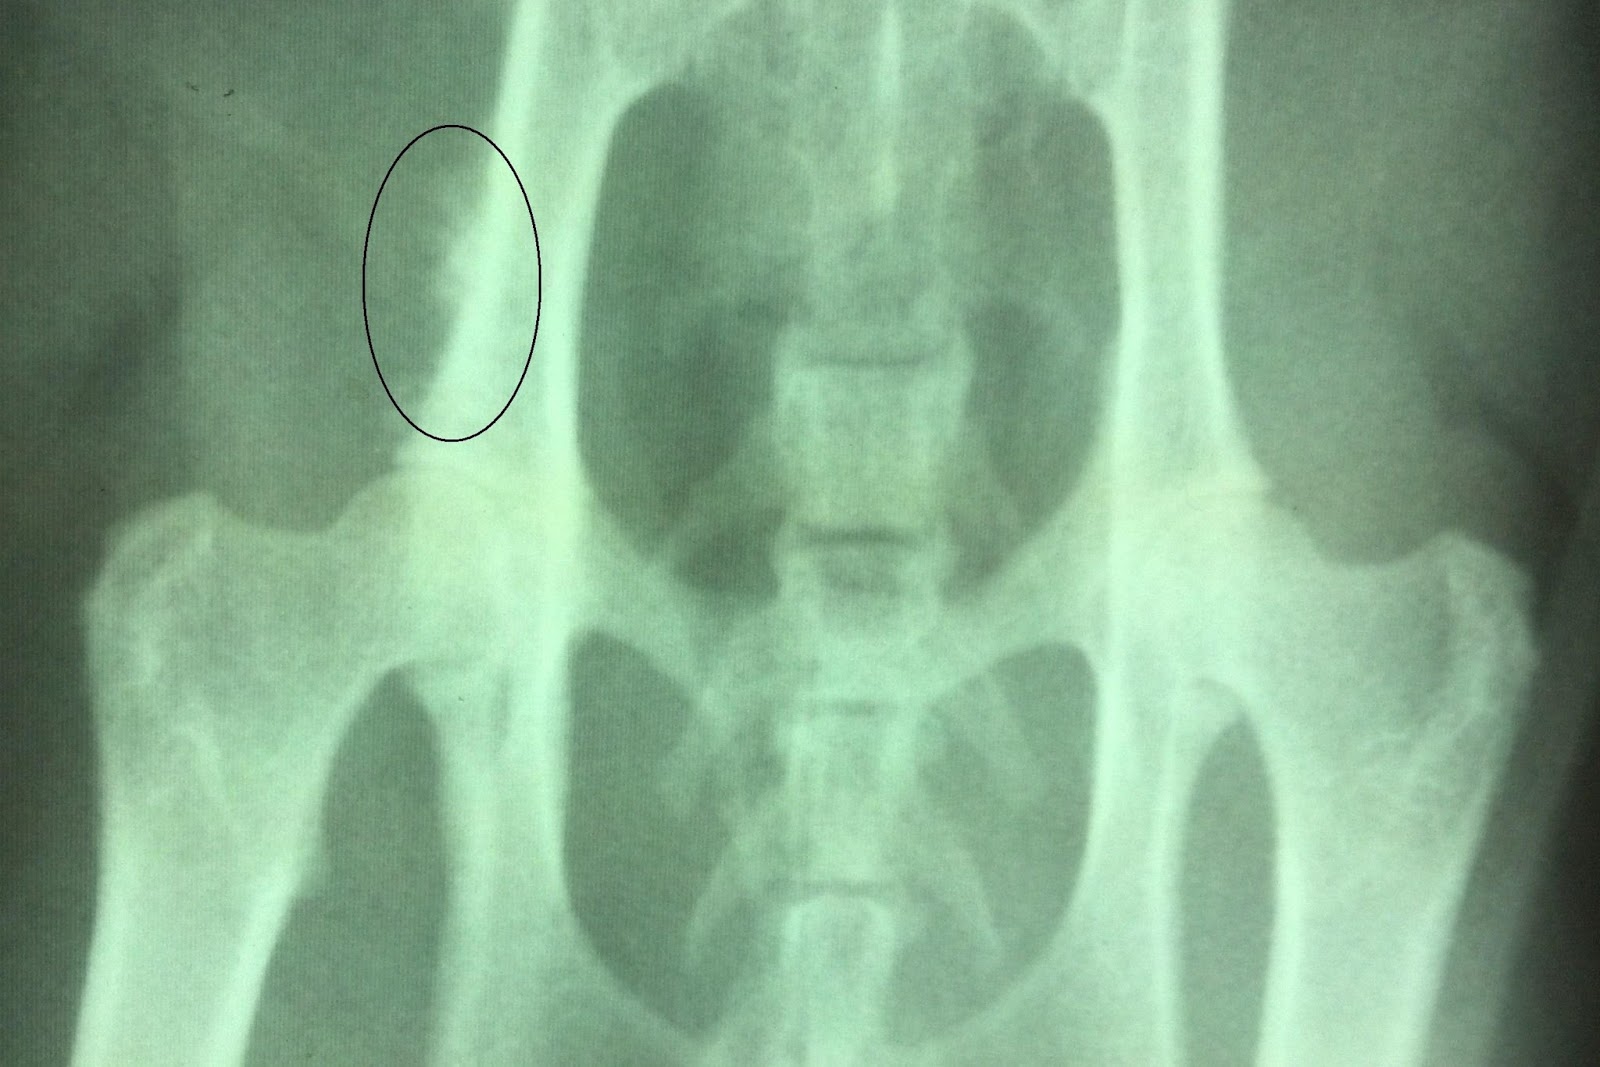

From www.sciencephoto.com

Valley fever, Xray Stock Image C039/4732 Science Photo Library Does Valley Fever Show Up On Xray If doctors think you may. Valley fever is an infection that occurs when the spores of the fungus coccidioides immitis enter your body through the lungs. Tests that a doctor may order to confirm a diagnosis of valley fever include: This rash can show up in different ways. Unfortunately, it is usually not possible to make a definite diagnosis without. Does Valley Fever Show Up On Xray.

Valley fever, Xray Stock Image C039/4734 Science Photo Library Does Valley Fever Show Up On Xray This rash can show up in different ways. Unfortunately, it is usually not possible to make a definite diagnosis without removing a part or the entire nodule by. Through a blood test, your doctor can check for antibodies against the fungus that causes valley fever. Apical fibronodular lesions with cavities and volume loss are seen on radiographs, which generally show. Does Valley Fever Show Up On Xray.